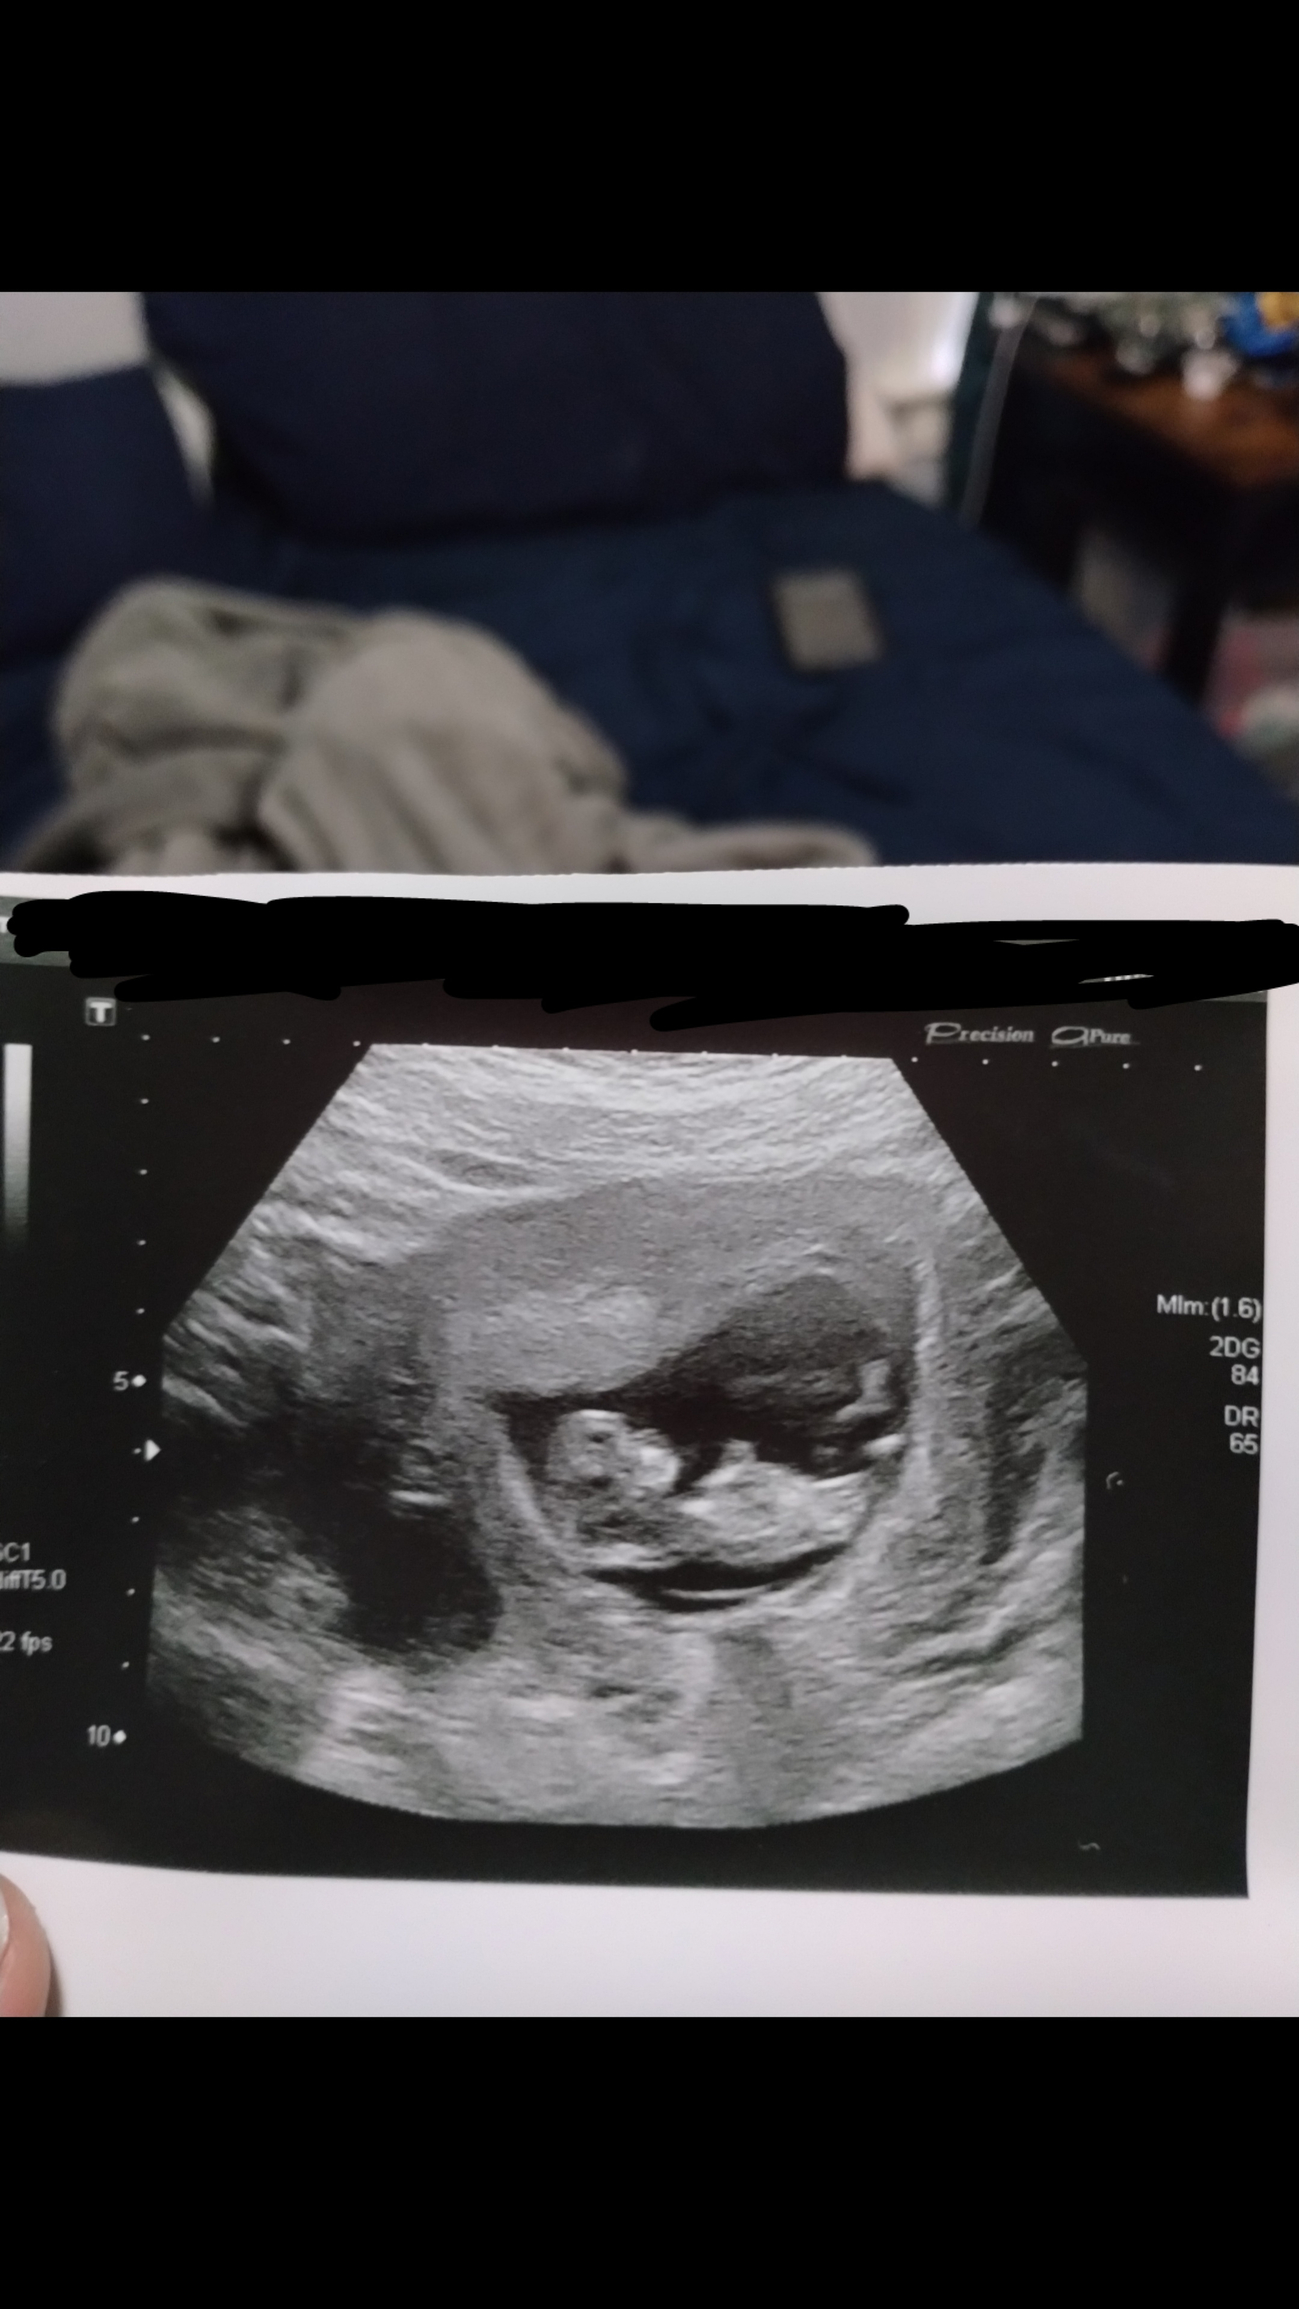

Got to see our little baby today! Measuring right on track, 7 weeks 1 day, and saw a beautiful little heartbeat of 144bpm! ❤️ I’m so relieved, we still have weeks to go to be out of the first trimester, but we never got to see the heartbeat with our previous loss.